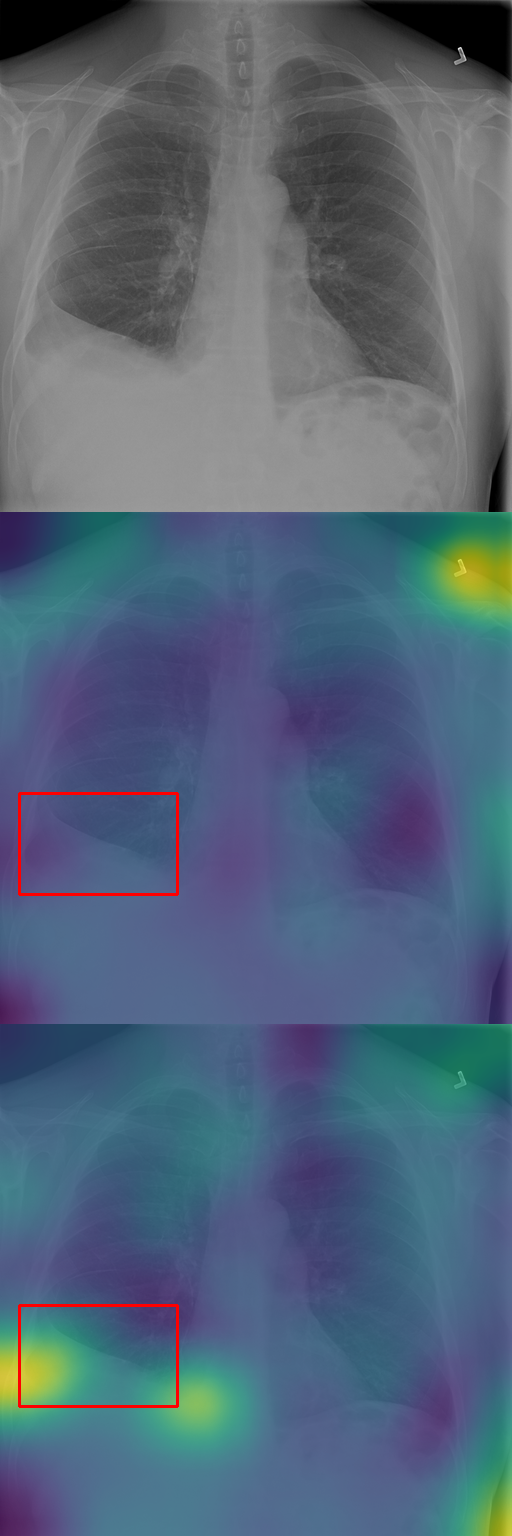

In Section 4.2, we discussed how typicality helps find relevant patches for an input label. In this section, we test this idea on completely different images: X-rays of patients who may suffer from a combination of various thorax diseases. We finetune Stable Diffusion on the ChestX-ray8 dataset [46] containing 108,948 frontal-view X-ray images annotated with 14 single-word disease-name labels. Experts annotated a test set of 879 images with 7 diseases with rectangular regions of interest (ROI) for each disease. For each image, we compute typicality per latent feature, interpolate the resulting typicality to the input dimension, and blur the resulting typicality map for visualization. In Fig. 11, we show the resulting typicality maps together with the ROI annotation before and after finetuning. Finetuning clearly improves the localization. We quantify this effect by computing the area under the precision recall-curve [5] (AUC-PR) associated with the ROIs. As reported in Fig. 11, we see consistent improvement of this measure when finetuning the network (from 3.2% to 9.6%), ranging from +3.5% for Pneumonothorax (from 3% to 6%) to +14.6% for Mass (from 2% to 16.6%), which are respectively the least and most localized diseases. Similar to our other experiments, finetuning uses only image labels without localization supervision.